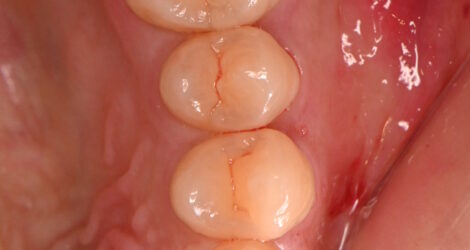

PGAインレーの症例

今回はPGAインレーの症例をご紹介します🦷

☆20代男性

☆クリーニングで虫歯発見

☆部位:左上6

処置前↓

処置後↓

🦷費用🦷

PGAインレー ¥82,500

金属代 ¥6,400/g×1,2グラム